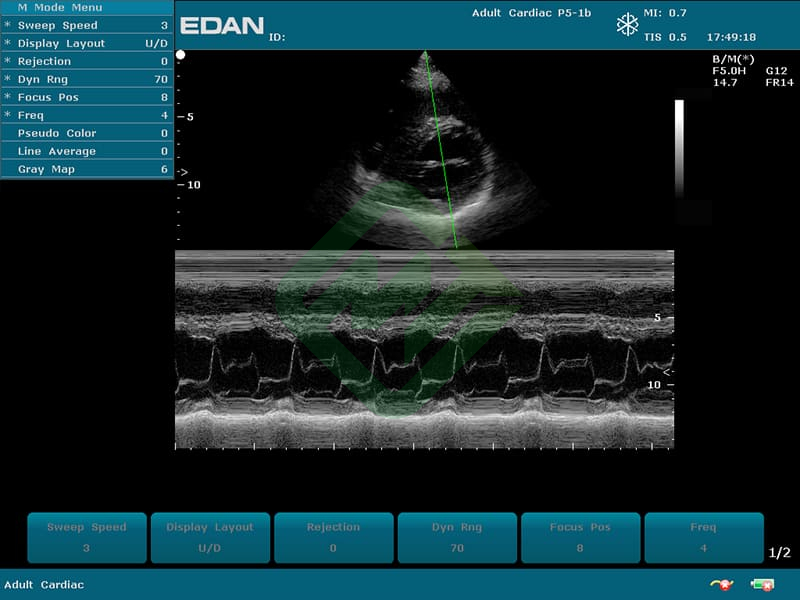

- Режимы сканирования: B, M, CDI, PW, CW, PDI, DPDI или B, M, ЦДК

— мультичастотные УЗ-датчики: линейный датчик Edan L742UB, конвексный датчик Edan C352UB, фазированный датчик Edan P5-1b

— фазированным P5-1b: частотный диапазон датчика 1,8–4,3 МГц, угол обзора 90°, глубина сканирования 320 мм, количество элементов 64 - Также для U50 подходят датчики (приобретаются отдельно):

- Датчик фазированный ультразвуковой P5-1b — 1 шт.